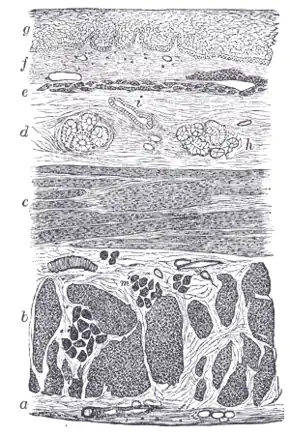

Section of the human esophagus. Moderately magnified.

Section of the human esophagus. Moderately magnified. -